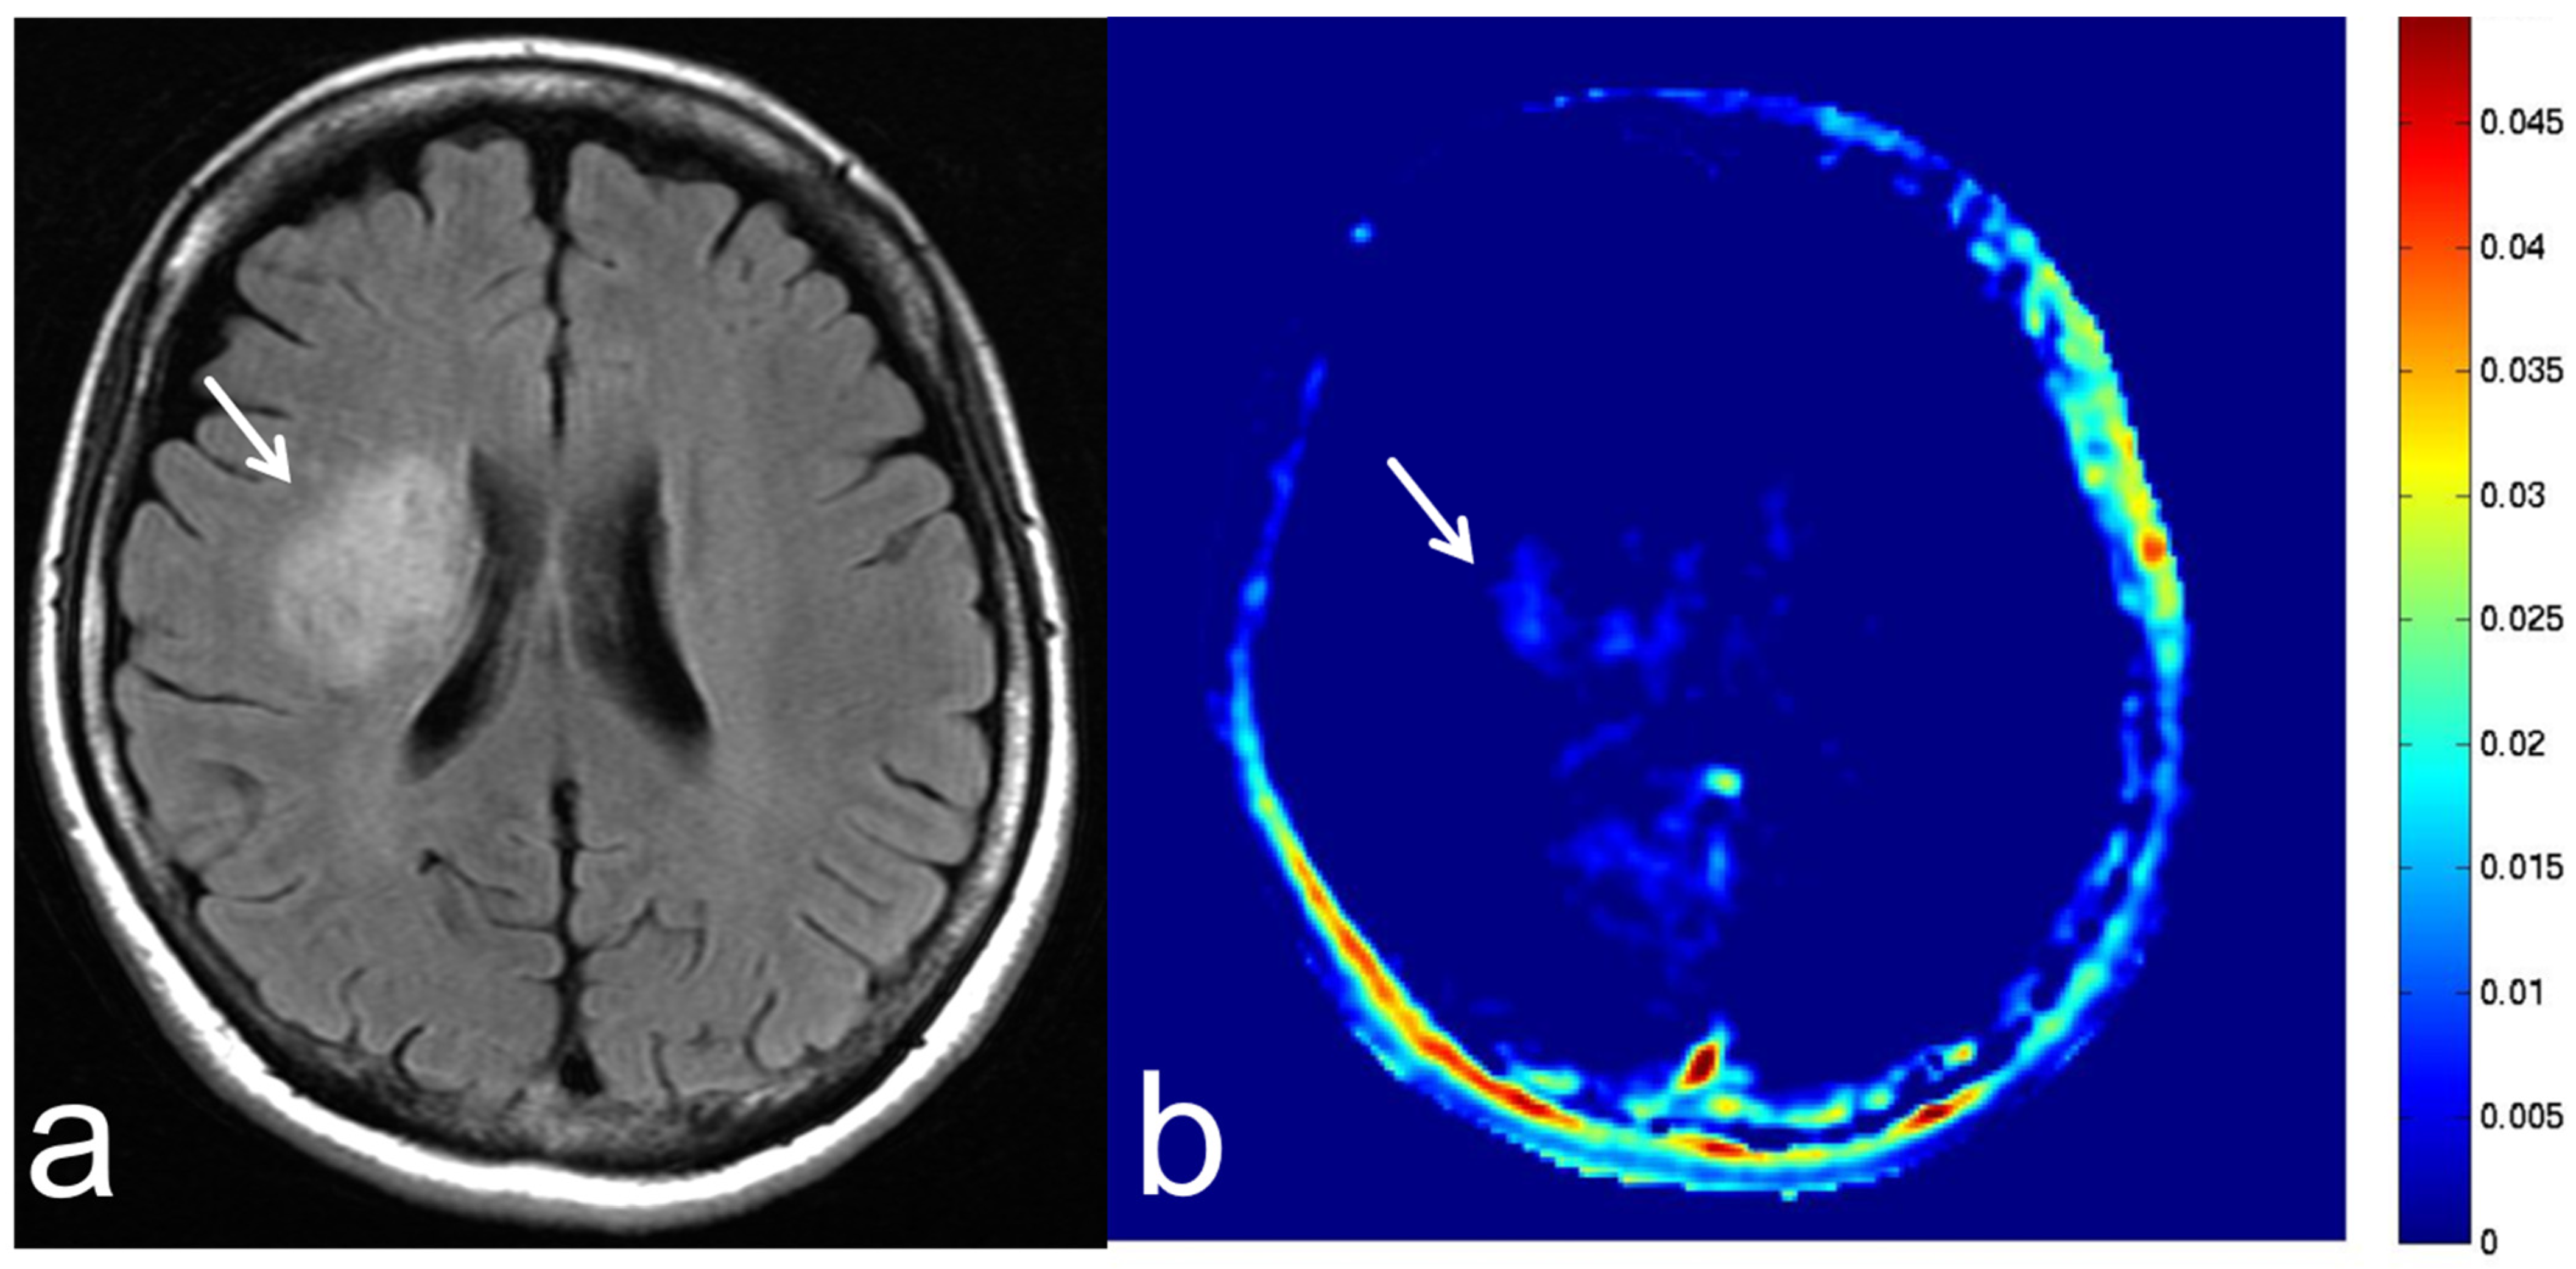

8.2. Leukoencephalopathy